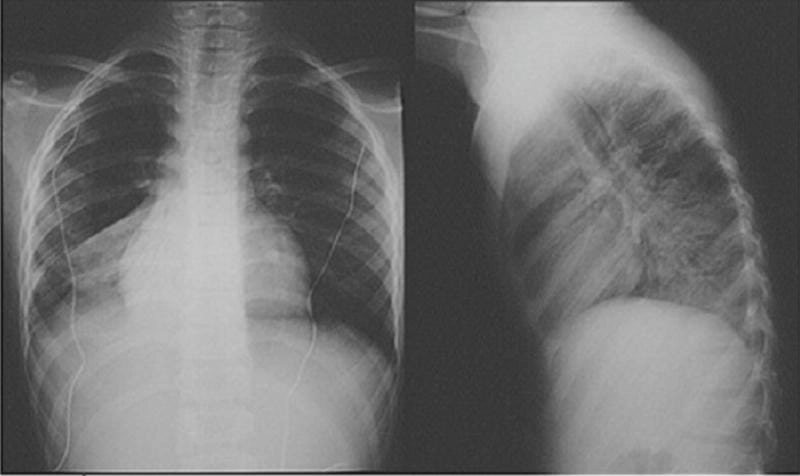

Hình ảnh bệnh lao phổi là tài liệu tham khảo quan trọng giúp người bệnh và bác sĩ dễ dàng nhận biết dấu hiệu bất thường. Việc quan sát hình ảnh X-quang, CT phổi giúp chẩn đoán chính xác mức độ tổn thương và đưa ra phương án điều trị kịp thời.

Bạn sẽ phải rùng mình khi chiêm ngưỡng hình ảnh bệnh lao phổi là như thế nào dưới ống kính y học thực tế. Những bức ảnh chụp X-quang cho thấy phổi bị tổn thương nặng, xuất hiện những đốm trắng mờ như bóng ma ám ảnh. Không chỉ là các tổn thương vật lý, đây còn là những “chứng tích sống” của căn bệnh âm thầm hủy hoại cơ thể qua từng hơi thở. Từ viêm nhẹ đến tổn thương lan rộng, hình ảnh bệnh lao phổi khiến người xem không thể rời mắt vì mức độ nghiêm trọng mà nó thể hiện rõ ràng qua từng chi tiết.

Cảnh báo: tổng hợp ảnh bệnh lao phổi chân thực này không dành cho người yếu tim. Đây là loạt hình ảnh y khoa được các chuyên gia sưu tầm và xác thực, ghi lại quá trình tiến triển của bệnh từ giai đoạn đầu đến giai đoạn nguy kịch. Từng mảng mô phổi bị ăn mòn, xơ hóa, hoại tử được phơi bày rõ nét dưới ánh sáng X-quang lạnh lùng. Những hình ảnh này không chỉ mang tính chất minh họa y học, mà còn là hồi chuông cảnh tỉnh cho bất kỳ ai còn lơ là với căn bệnh nguy hiểm này.